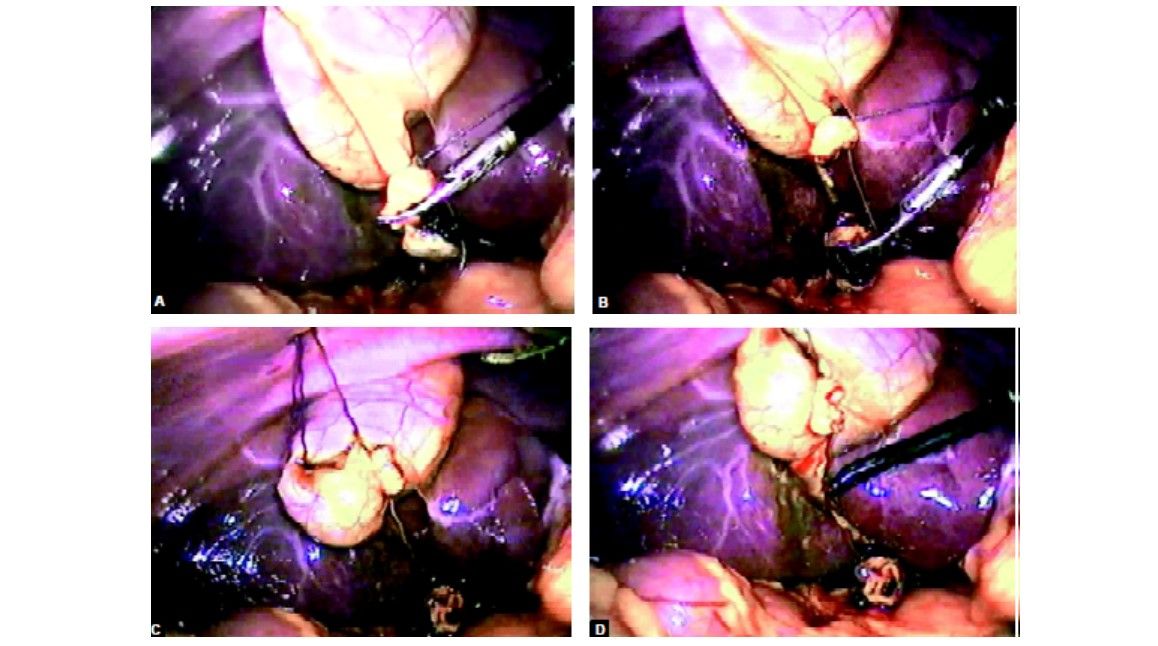

Another Vicryl is applied over Hartsman pouch to provide anterolateral traction. Any leak from the gallbladder is irrigated and sucked nicely with the help of suction irrigation instrument

Dissection of the cystic pedicle is performed by Maryland

Clip or extracorporeal Meltzer knot is applied over cystic artery and duct

The extracorporeal knot of the cystic duct is used to pull the neck up and to expose bed of the gallbladder

Any leak should be sucked and gallbladder is separated with the help of hook